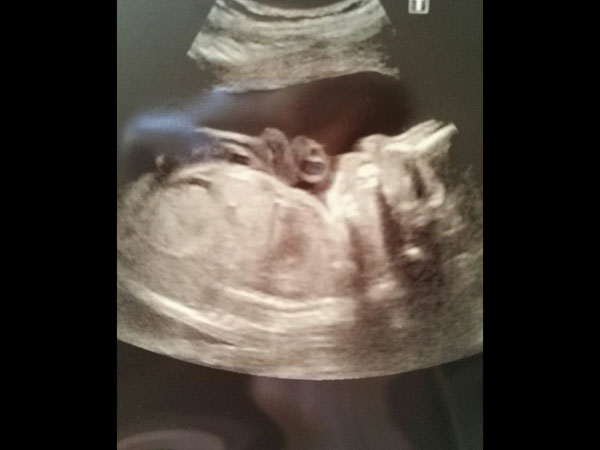

குழந்தை பிறந்த பிறகு, முதல் ஆறு வாரங்களுக்கு நோயாளி தாய்ப்பால் ஊட்டினார் மற்றும் அந்த நேரத்தில், குழந்தை நல மருத்துவர் "குழந்தையின் வளர்ச்சி, உணவு, குடல் பழக்கம் ஆகியவை வளர்ச்சிக்கு ஏற்றதாக இருந்தன" என்று கூறியதாக அந்த ஆய்வு தெரிவித்தது. அதன் பின் அவளால் குழந்தைக்கு போதுமான அளவு பால் உற்பத்தி செய்ய முடியவில்லை என்பதால் தாய்ப்பாலுடன் சேர்த்து பவுடர் பாலும் கொடுக்கத் தொடங்கினாள் என்றும் கூறப்படுகிறது. ஆறு மாதத்தில் அந்த குழந்தை ஆரோக்கியமாக சந்தோஷமாக மிகவும் அழகாக இருந்ததாக இந்த ஆய்வின் துணை எழுத்தாளர் ரெய்ஸ்மேன் கூறுகிறார்.